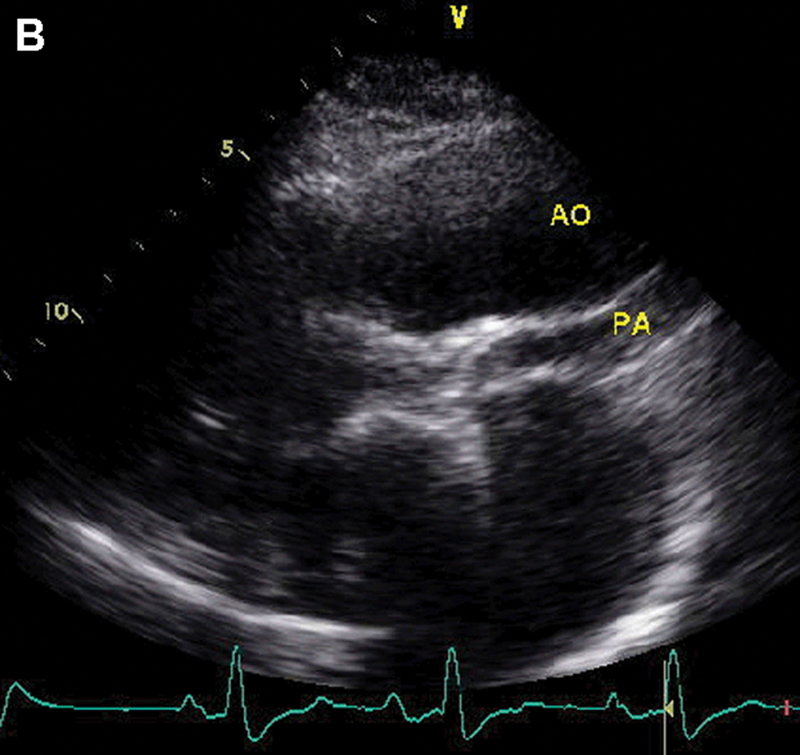

فحوصات تشخيصية لبعض امراض القلب والشرايين التاجية